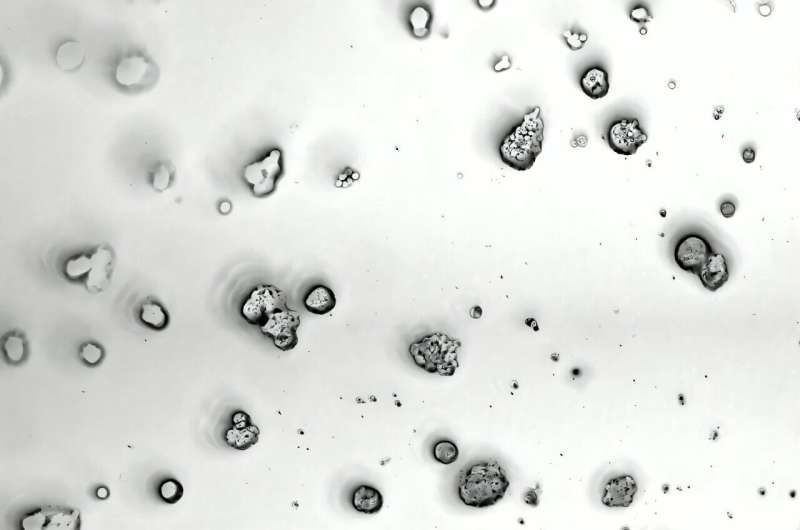

Now, research led by Christopher J. Lengner and M. Andrés Blanco of the School of Veterinary Medicine has identified two genes that suppress metastasis in preclinical models of colorectal cancer. The study is published in the Proceedings of the National Academy of Sciences.